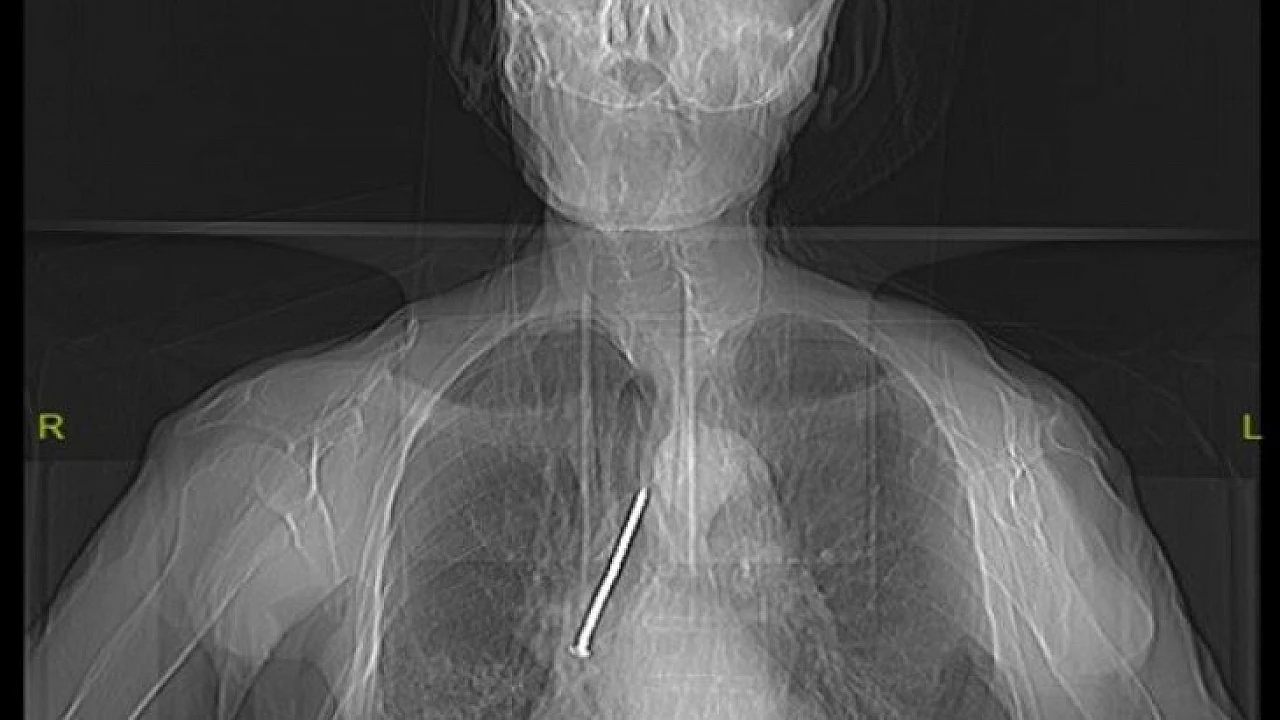

Elazığ’da, boynundan nefes borusuna açılan açıklık aracılığıyla solunumunu sağlayan Keko Ateş (91), öksürük ve nefes darlığı şikayetiyle Fethi Sekin Şehir Hastanesine başvurdu. Burada yapılan tetkik ve muayeneler sonucu yaşlı adamın nefes alıp verdiği boşluğu temizlemek için kullandığı 10 santimetrelik çivinin soluk borusuna kaçtığı belirlendi. Hayati tehlike oluşturan çivi, Göğüs Cerrahi Uzmanı Dr. Öğretim Üyesi Murat Kılıç tarafından “Rijit Bronskoskopi” işlemi ile çıkarıldı. Yaşlı adam çivinin çıkarılmasından kısa süre sonra hasta taburcu edildi.

Hızlı bir şekilde müdahale edilmediği takdirde hayatı tehlikeye atabilen bir durumla karşı karşıya kaldıklarını belirten Dr. Kılıç, "Larenks kanseri nedeniyle 24 yıl önce boynundan nefes borusuna açılan açıklık aracılığıyla nefes alıp verebilen hasta, nefes borusundaki bu açıklığı temizlemek amacıyla kullandığı 10 santimlik çiviyi soluk borusuna kaçırmış. Bu nedenle gelişen öksürük ve nefes darlığı şikayeti ile önce başka bir sağlık merkezine başvurmuş, ardından Fethi Sekin Şehir Hastanemiz Göğüs Cerrahisi Kliniğine yönlendirilmiş. Biz de hastanede 91 yaşındaki hastamıza çektiğimiz tomografide soluk borusu içerisinde, sağ akciğer içerisine doğru kaçmış olan çiviyi tespit ettik” dedi.